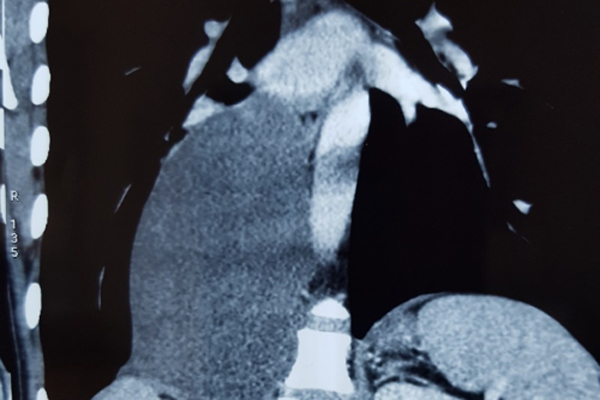

Hình ảnh khối u kích cỡ lớn trong lồng ngực nam thanh niên

Kết quả chụp cắt lớp vi tính 64 dãy và cộng hưởng từ xác định khối trung thất sau phải có dạng tổ chức đặc kích thước 15x9 cm, đè đẩy vòm hoành phải xuống dưới, chèn ép tĩnh mạch chủ, nhu mô phổi.

Giải phẫu bệnh chẩn đoán là u hạch thần kinh xuất phát từ hạch giao cảm. Bác sĩ chỉ định phải phẫu thuật sớm, càng để lâu khối u càng lớn, chèn ép vào các cơ quan lân cận cản trở tuần hoàn, hô hấp.